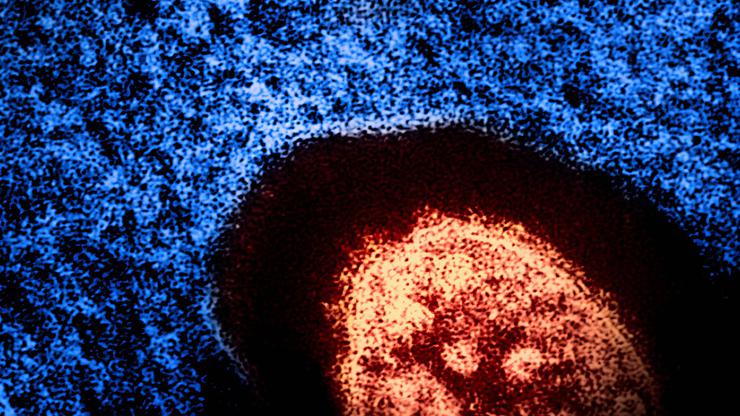

Brian W.J. Mahy, BSc, MA, PhD, ScD, DSc This transmission electron micrograph (TEM) revealed the ultrastructural appeara